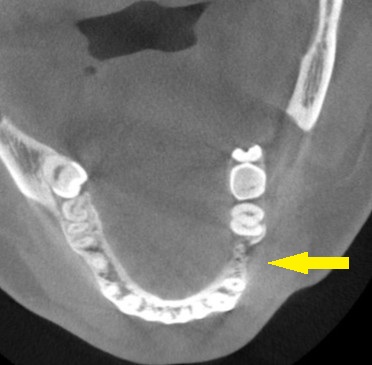

CTを撮影してみると、確かに、骨幅が狭く、十分な骨の厚みを確保してインプラントを長期に安定した状態にしたいとなると、骨を増やす手術が必要でした。

下の写真に手術前後のCTを示します。